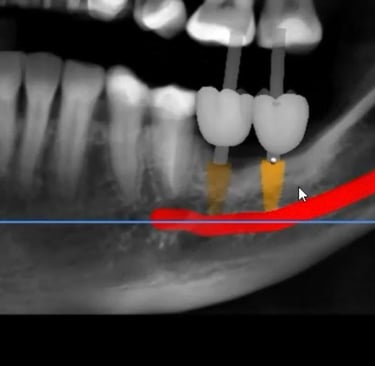

Comparação do Planejamento com o Resultado

Aspecto Tomográfico Final do Enxerto e Planejamento Digital para o Implante

Pouco osso? A cirurgia guiada pode ser a solução.

Mesmo quando há pouca quantidade de osso, muitas vezes não é preciso fazer enxerto.

Com o uso de tecnologia digital em 3D, a cirurgia guiada permite planejar com precisão milimétrica a posição dos implantes, aproveitando ao máximo o osso disponível.

Esse planejamento detalhado também possibilita desviar de estruturas importantes, como o canal mandibular (por onde passa um nervo sensível) e o seio maxilar (uma cavidade natural próxima aos dentes superiores), tornando o procedimento mais seguro e previsível.

Caso da cirurgia guiada dispensando o enxerto - Imagens originais — nenhuma contém retoques